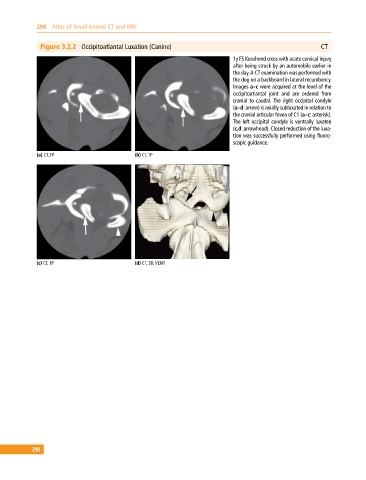

Figure 3.2.2 Occipitoatlantal Luxation (Canine) CT

1y FS Keeshond cross with acute cervical injury

after being struck by an automobile earlier in

the day. A CT examination was performed with

the dog on a backboard in lateral recumbency.

Images a–c were acquired at the level of the

occipitoatlantal joint and are ordered from

cranial to caudal. The right occipital condyle

(a–d: arrow) is axially subluxated in relation to

the cranial articular fovea of C1 (a–c: asterisk).

The left occipital condyle is ventrally luxated

(c,d: arrowhead). Closed reduction of the luxa-

tion was successfully performed using fluoro-

scopic guidance.

(a) CT, TP (b) CT, TP

(c) CT, TP (d) CT, 3D, VENT